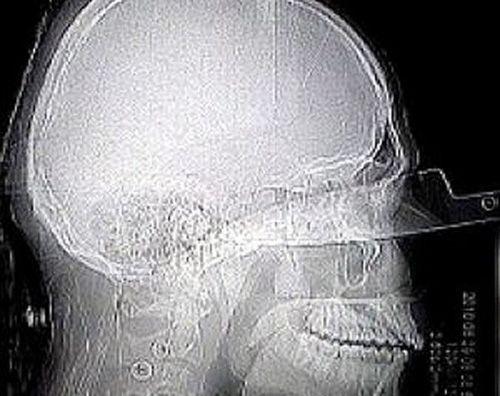

今年24岁的哥伦比亚男子杰德·托里斯·莫塔参加完朋友聚会回家途中不幸遭遇劫匪,他挨了一拳后试图驾驶摩托车逃跑,却被劫匪用一把约20厘米长的匕首刺入左眼。

莫塔忍受着匕首插在颅骨中的巨大痛苦,被医护人员从一家医院送到另一家,寻找有能力为他做手术的医生。直到12个小时之后,匕首才被从莫塔的眼中取出。尽管失去了一只眼睛,但是这个顽强的小伙子仍然认为自己非常幸运,因为他能够从如此可怕的伤害中幸存下来。